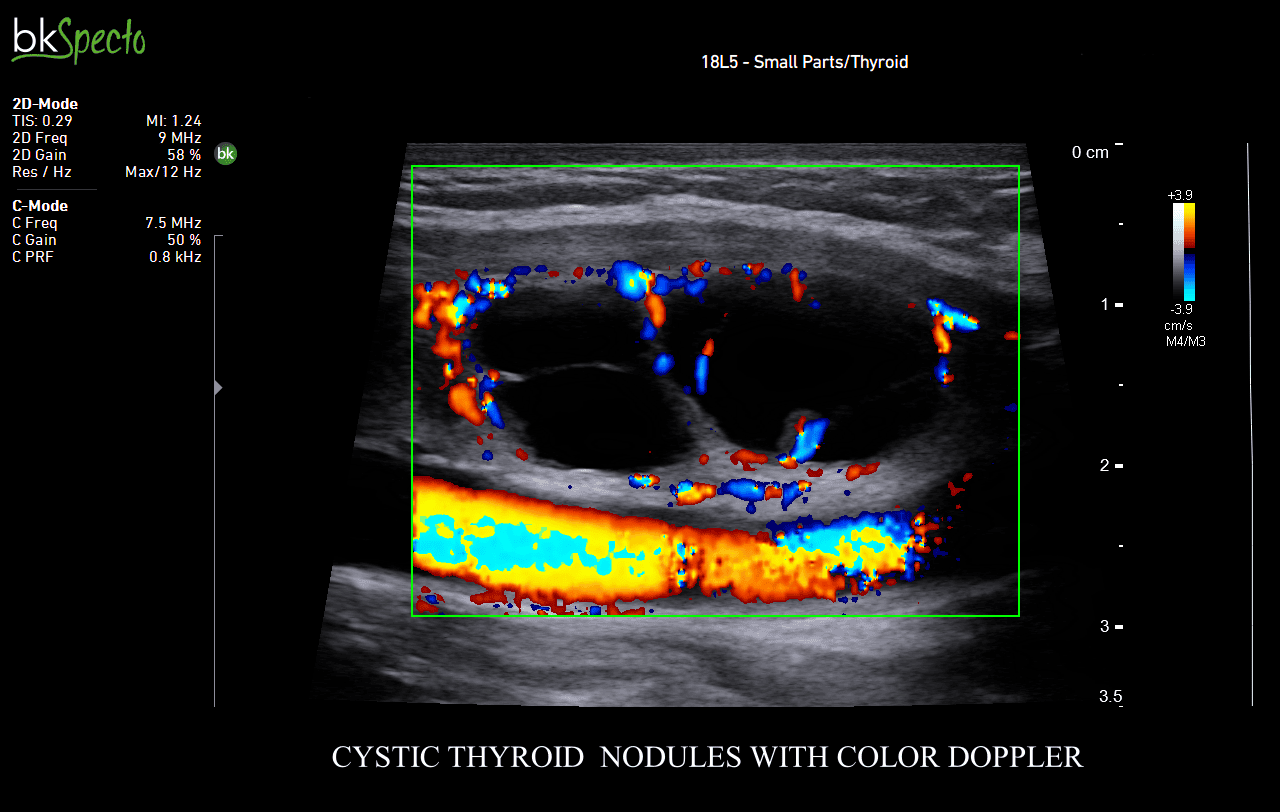

BkSpecto là hệ thống siêu âm chuyên về các thủ thuật can thiệp cho các chuyên khoa: Tiết niệu, gây mê, cơ, tuyến vú, tuyến giáp, sản phụ khoa và hậu môn trực tràng.